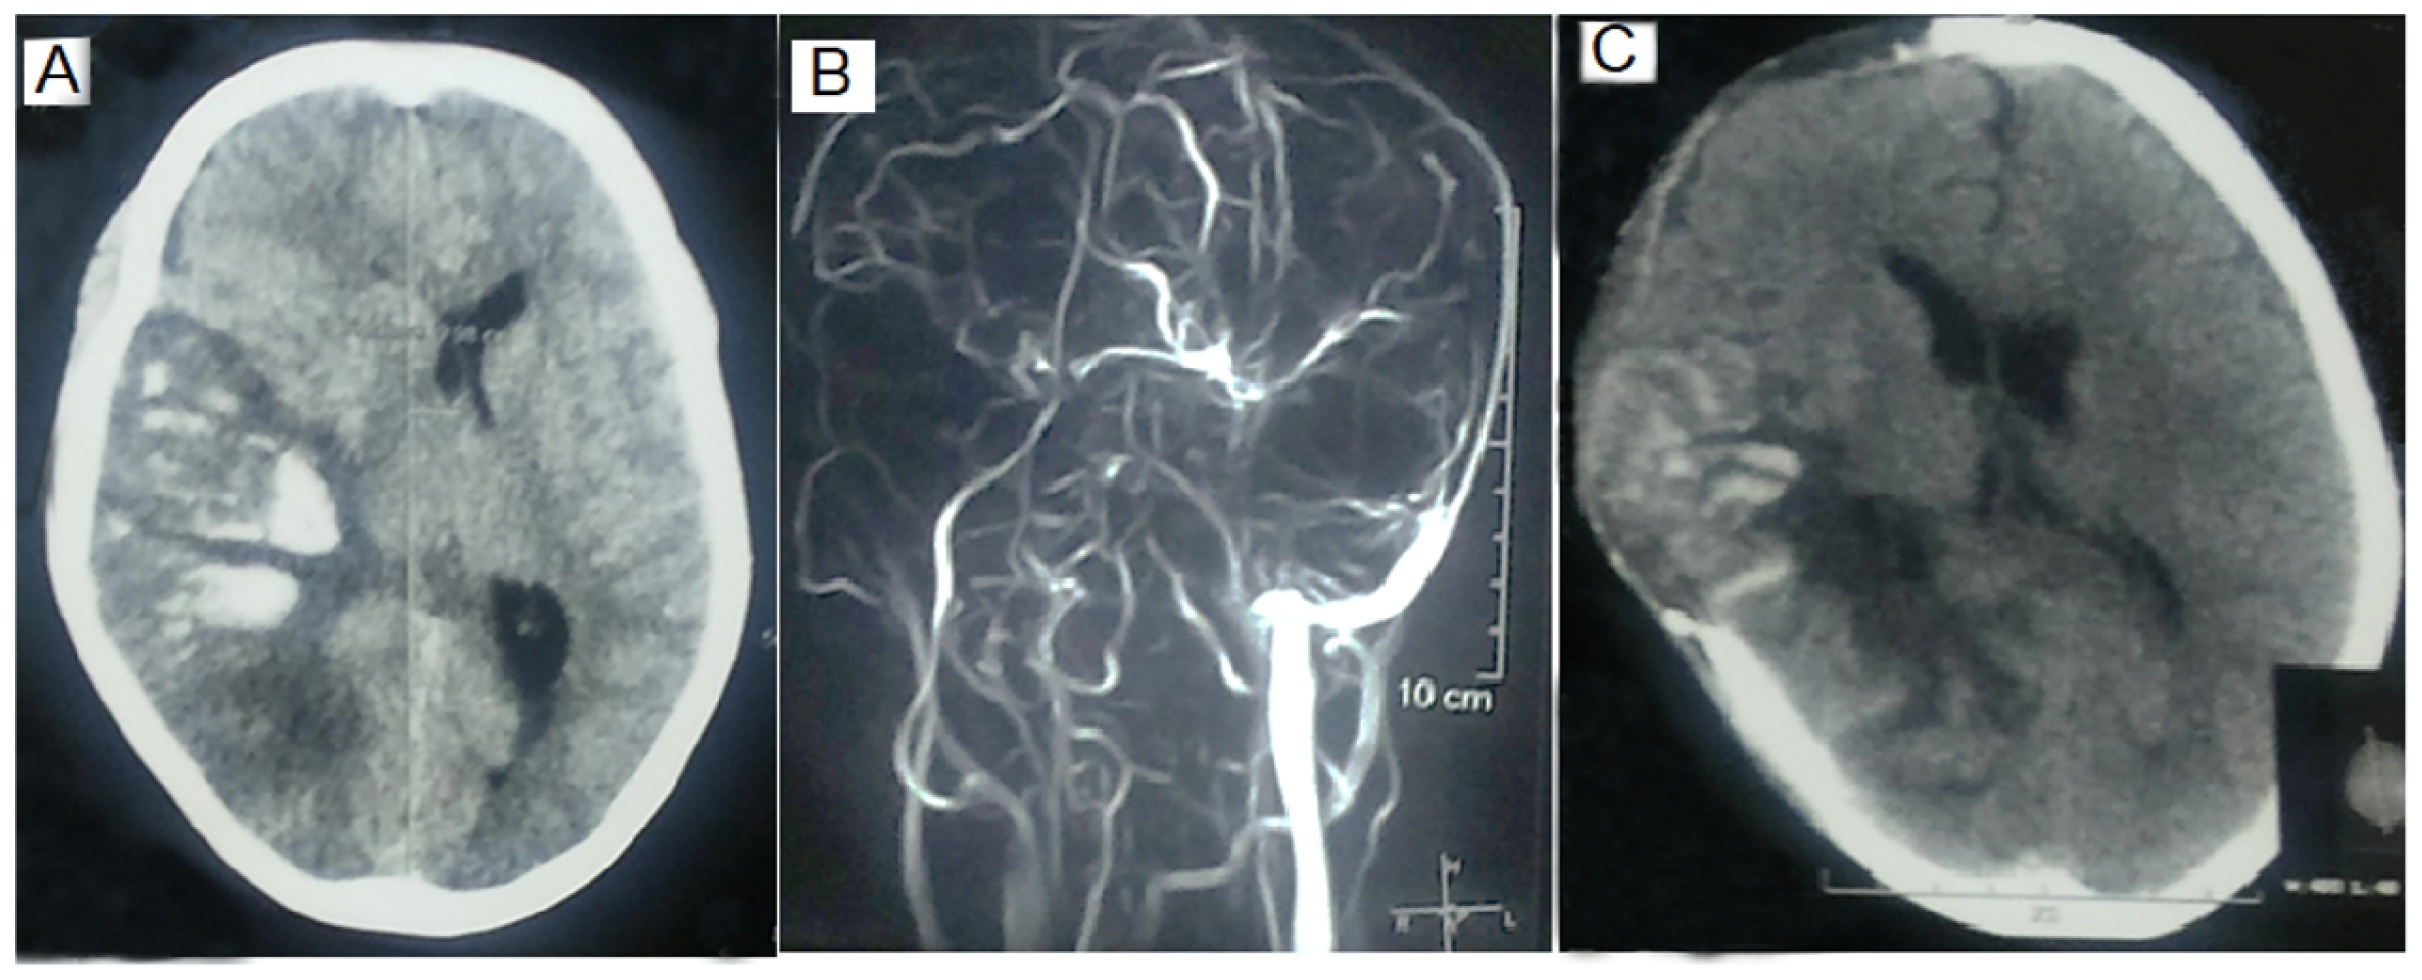

3.2. MRI and MRV Findings

3.4.2. Comparison of MRV and MRI Findings